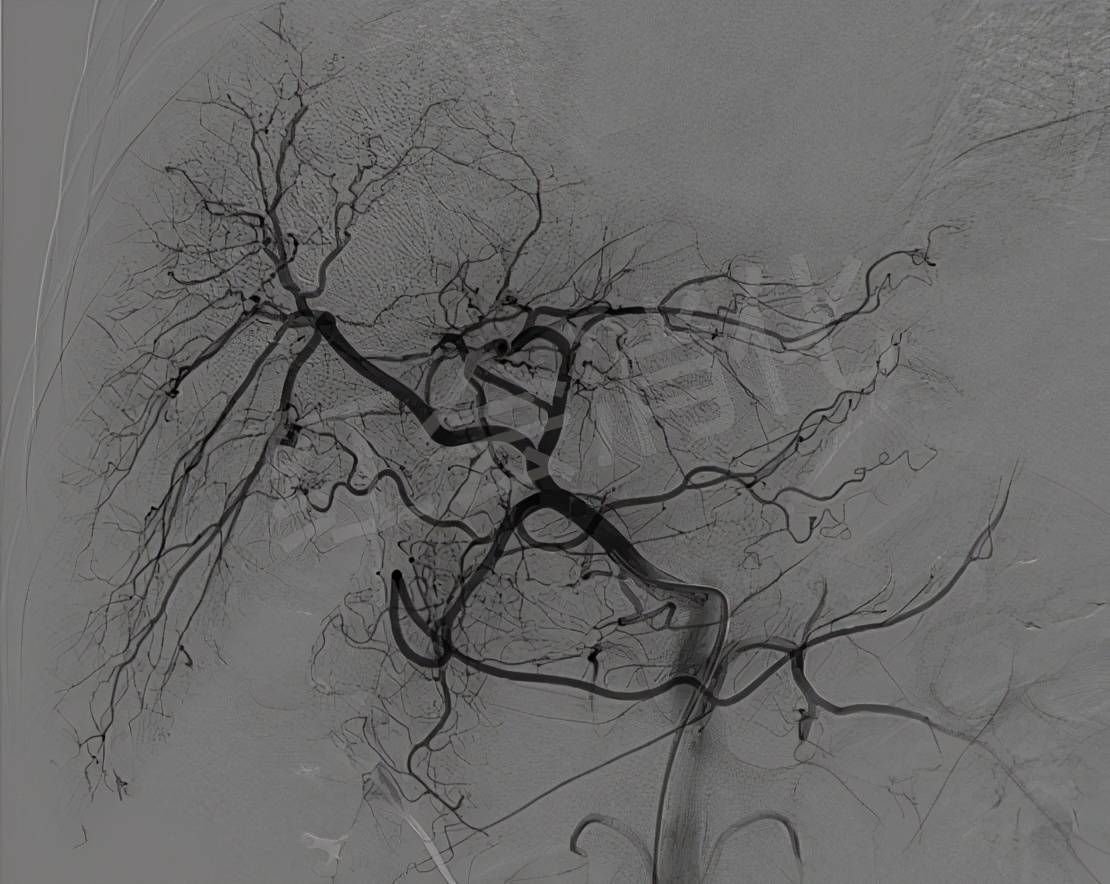

栓塞后肝动脉造影 , 肿瘤周围的动脉丛消失 , 动脉化疗栓塞成功

文章图片